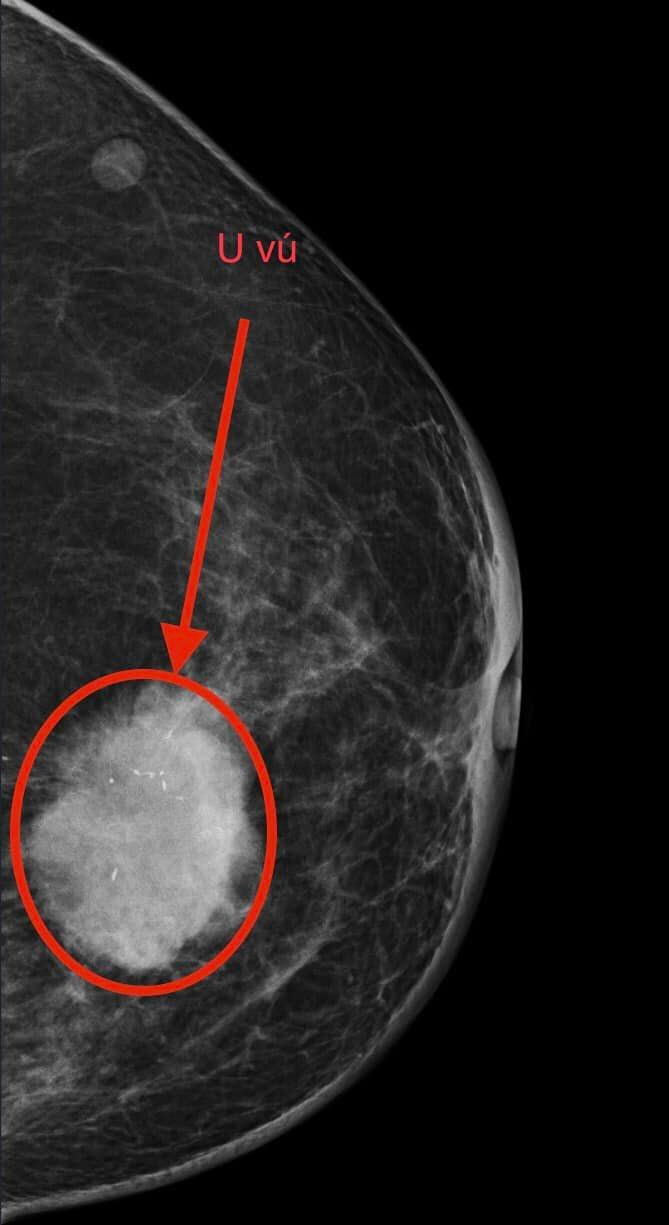

| Kết quả thăm của bệnh nhân ung thư tuyến vú đã di căn hạch. Ảnh BVCC |

Qua thăm khám, bác sĩ xác định khối u tuyến vú trái kích thước 4x4 cm, mật độ cứng chắc, ranh giới không rõ ràng, kèm theo hiện tượng sưng đỏ, đau nhức và tụt núm vú. Hạch nách trái cũng nổi rõ. Lần này, may mắn là gia đình đã đồng ý cho bác thực hiện sinh thiết và chọc tế bào hạch nách.

Kết quả không ngoài dự đoán: Ung thư tuyến vú đã di căn hạch.